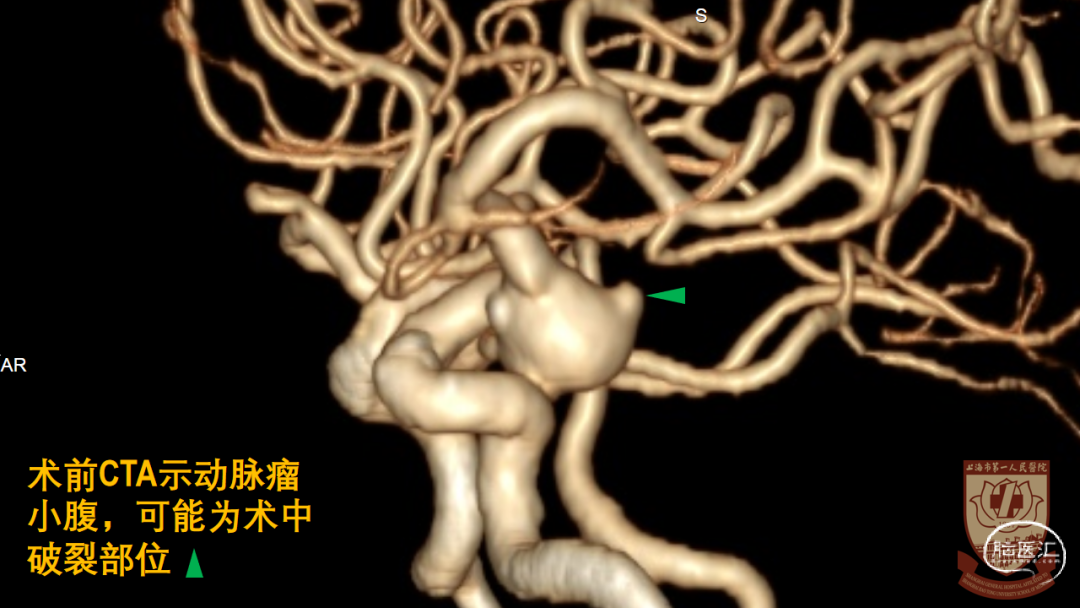

大型动脉瘤,形态复杂:发自ICA后外壁,宽颈、后交通动脉自瘤颈发出

术中早期破裂造成手术困难

动脉瘤形态复杂

出血汹涌,出血部位不明